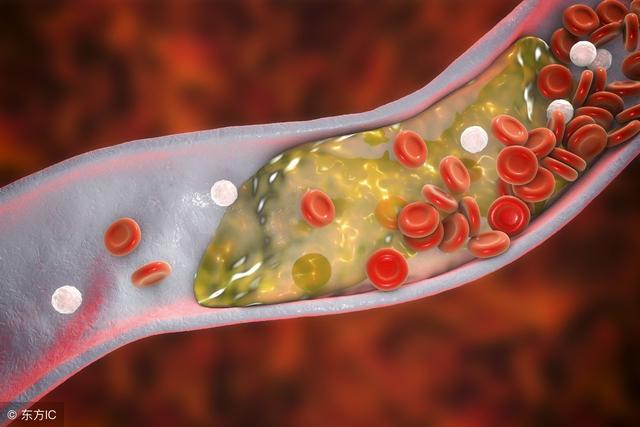

其实,正常的胆固醇量一般是小于5.8的。一般情况下,儿童和成人的胆固醇的正常值不同,是有很大的差别的。因为生理等各方面的不同,儿童的胆固醇的正常值一般要低一点,是3.12~5.20毫摩/升(120~200毫克/分升)。而成人的胆固醇的正常值的范围稍大一点,一般就是2.86~5.98毫摩/升(110~230毫克/分升)。所以,如果发现自己的胆固醇的检查结果显示的是7.5,那这就是属于高血脂症了。如果控制不好的话,很容易导致发生动脉粥样硬化的,有可能还会引发一些心脑血管类的疾病。

总胆固醇量高于7.5,还是属于胆固醇偏高的情况,所以此时就不要再吃胆固醇含量比较高的食物,比如各种蛋黄和动物的内脏还有动物的脑部。要积极地控制自己的饭量和所摄入的糖份的量,饮食还是相对应该清淡一点,不要喝酒。同时,还要检查一些看看自己是否患有肝病。因为有肝病的话就要引起重视了,并不是随便找个有肝病就不是随便找个医生就能治好的,一定要去正规的医院。